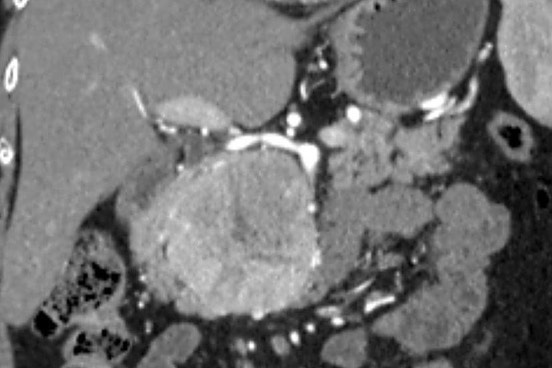

«Միքայելյան» համալսարանական հիվանդանոցում հերթական բարդ վիրահատությունն է իրականացվել, հեռացվել է ենթաստամոքսային գեղձի գլխիկի մեծ ուռուցք ավելի քան 10սմ տրամագծով, որը սերտ հպված էր միջընդերային զարկերակին և երակին:

Առհասարակ ենթաստամոքսային գեղձի գլխիկի մեծ չափի ուռուցքները համեմատաբար քիչ են հանդիպում: Առավել քիչ են հանդիպում այն դեպքերը, երբ գեղձի գլխիկի մեծ չափերի ուռուցքը չի առաջացնում մեխանիկական դեղնուկ: Համալսարանական հիվանդանոցի Վիրաբուժության կլինիկա է դիմել 62 տ. կին՝ գանգատվելով ցավից և ծանրության զգացումից վերորովայնային (էպիգաստրալ) շրջանում:

Կատարվել է պանկրեատոդուոդենալ մասնահատում, տեխնիկական դժվարություններով ուռուցքն անջատվել է վերին միջընդերային երակից և զարկերակից:

Հեռացված հյուսվածքի հետազոտությամբ հայտնաբերվել է ենթաստամոքսային գեղձի գլխիկի նեյրոէնդոկրին ուռուցք: